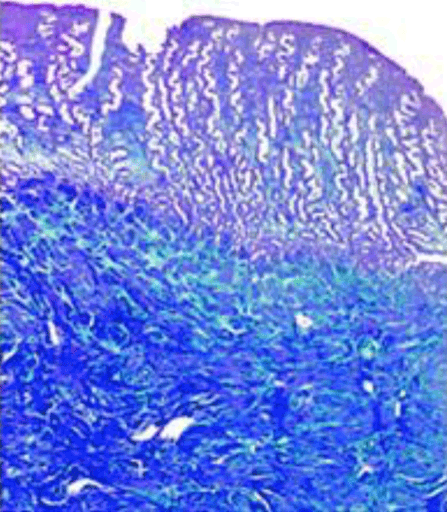

Ovocytes en métaphase II maturés in vitro à partir de follicules primaires

Pr Patricia Fauque

CHU - Dijon

Le développement complet des ovocytes peut-il être réalisé in vitro à partir de tissu ovarien humain ? Le développement complet des ovocytes cultivés in vitro à partir de follicules primordiaux jusqu’à maturation finale (MIV) a déjà été réalisé chez la souris et a permis l’obtention de souriceaux vivants. Des ovocytes matures sur le plan méiotique ont également été obtenus à partir de...